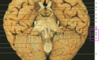

State where this stroke has occured

Right MCA